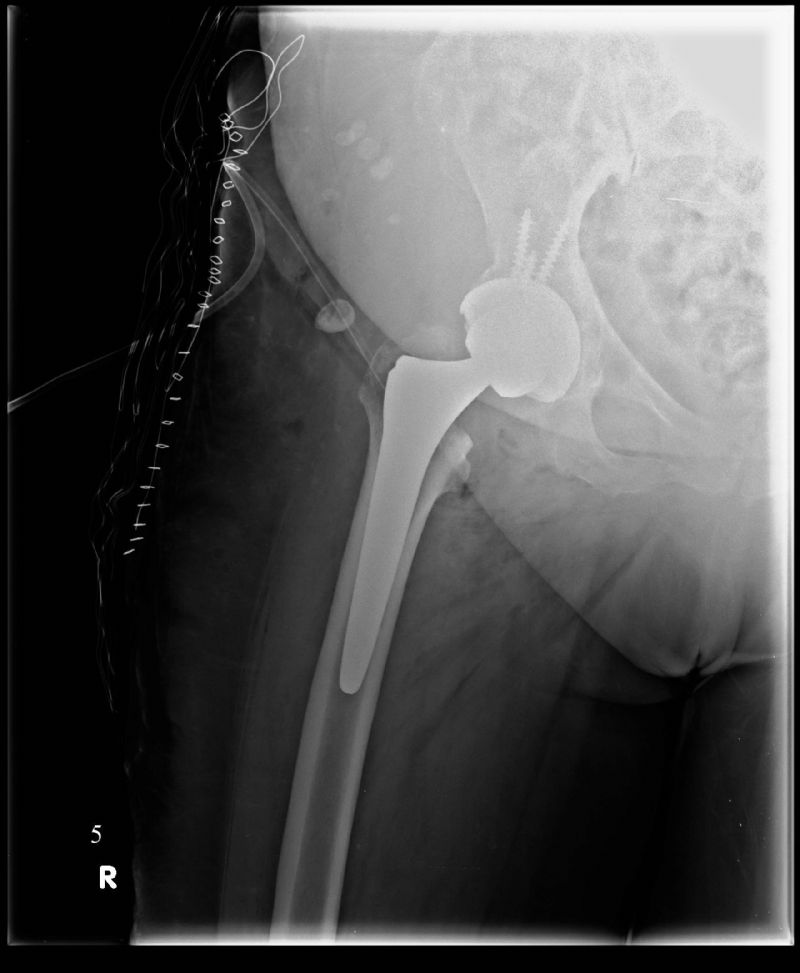

Total Kalça Protezi

Total Kalça Protezi Örnek Olgular